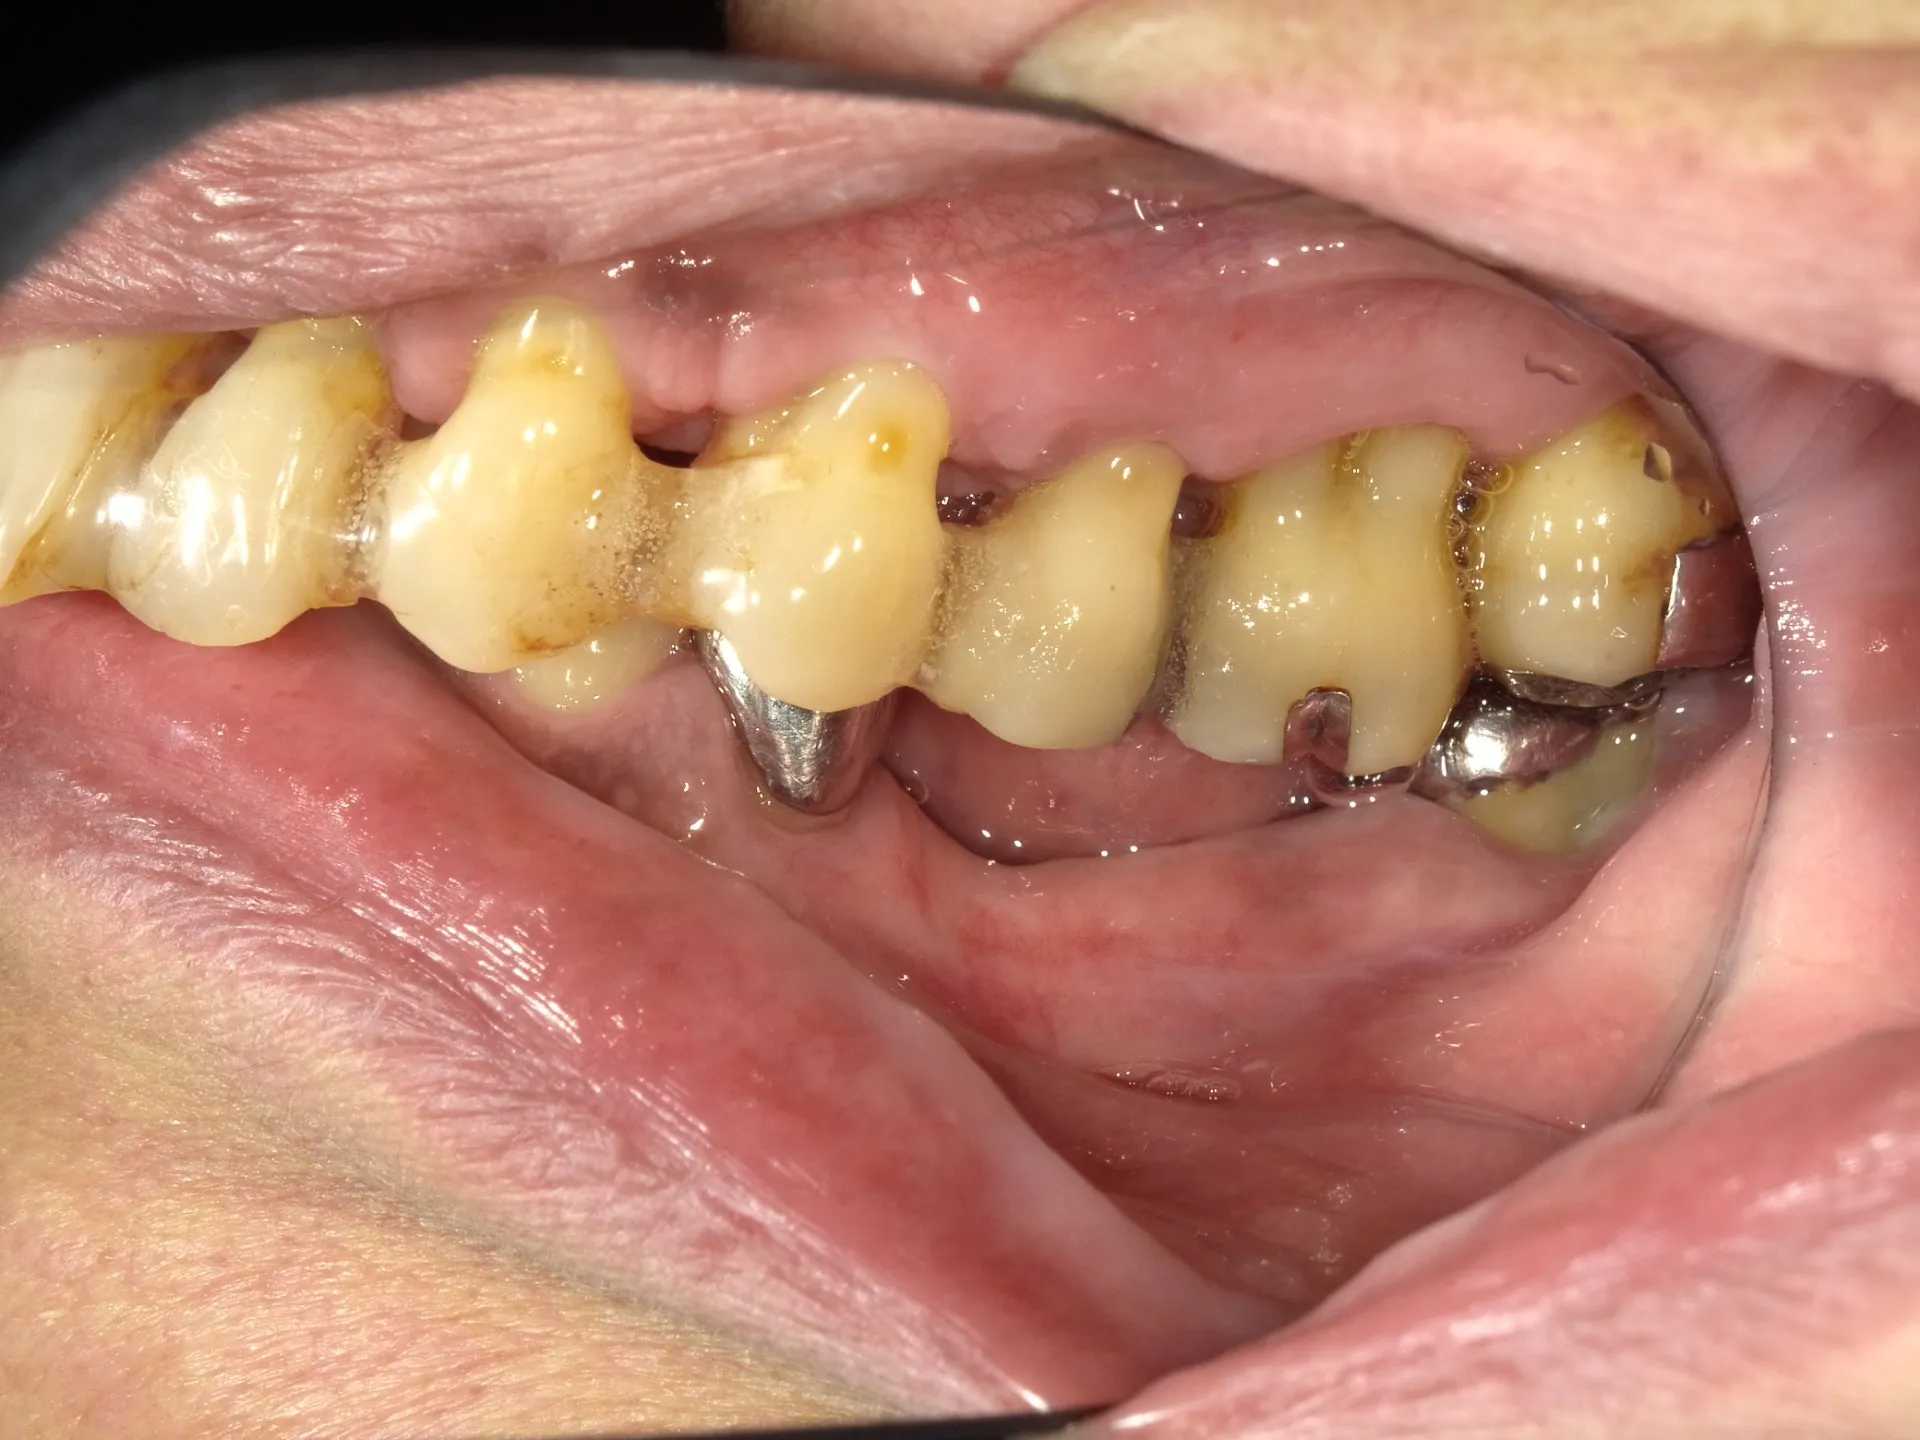

👆20年間SRPを続けてきた方

20年間、真面目にSRPを続けてきた方が、当院に転院された。

その歯茎の状態。